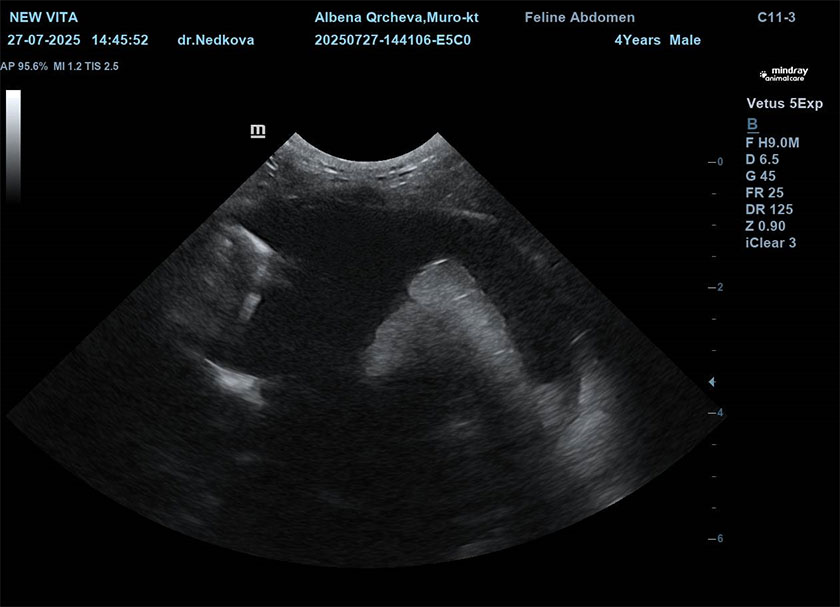

Ехокардиографията включваща и доплерово изследване е предпочитат неинвазивен метод на диагностика. Тя е изключително безопасна и с висока диагностична стойност. Чрез нея оценяваме морфологично и функционално всички части на сърцето. Най-често се установява концентрична хипертрофия на стената на лява камера, септумната преграда, увеличено ляво предсърдие, наличие на тромби в лявото предсърдие.